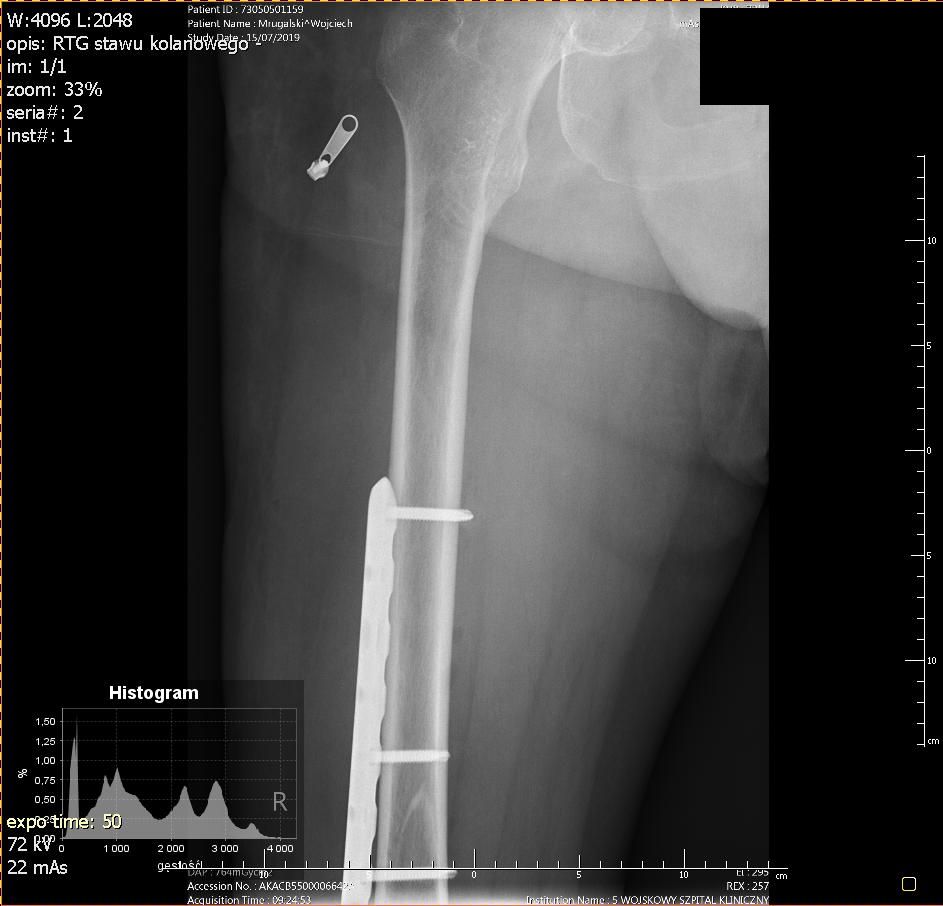

Przyjechałem na SOR. W wielkim skrócie to rejestracja, rentgen i diagnoza: złamanie spiralne 1/3 dalszej trzonu kości udowej prawej i zakwalifikowany do operacji.

Operacja zaczęła się około 13, a o 15 byłem na sali pooperacyjnej. Lekarze coś tam do mnie gadali, maszyny pikały, pielęgniarka co chwilę mnie szturchała bym oddychał. Gdyby nie to, że byłem taki senny to bym jej coś powiedział ale nie miałem sił. Wtedy chciałem ją zabić :) Koło godz. 17 już bardziej kumałem. Przyszli lekarze i powiedzieli mi, że wszystko jest ok, że mam w nodze płytkę, śruby i drut tytanowy. Z tym ostatnim przed operacją był problem bo był tylko stalowy ale na szczęście udało się w ostatniej chwili odszukać tytanowy drut i okręcić nim kość.

Ktoś może zapytać jaka to różnica między tytanem, a stalowym implantem? W przypadku implantów stalowych nie mogę korzystać z rezonansu magnetycznego. Chodzi o to, że w stalowym obiekcie wytwarzają się prądy wirowe pod wpływem silnego pola elektromagnetycznego z rezonansu magnetycznego, a to zaś powoduje duże nagrzanie elementów stalowych. Dzięki implantom tytanowym nie będę musiał ich wyjmować oraz będę mógł bez przeszkód robić rezonans. To tyle z "wykładu" o fizyce.

Jestem pełen uznania i wdzięczności za opiekę i profesjonalne podejście do sprawy. Operacja została wykonana w Klinice Chirurgii Urazowej i Ortopedii, 5 Wojskowego Szpitala Klinicznego z Poliklinika w Krakowie przy ul. Wrocławskiej.